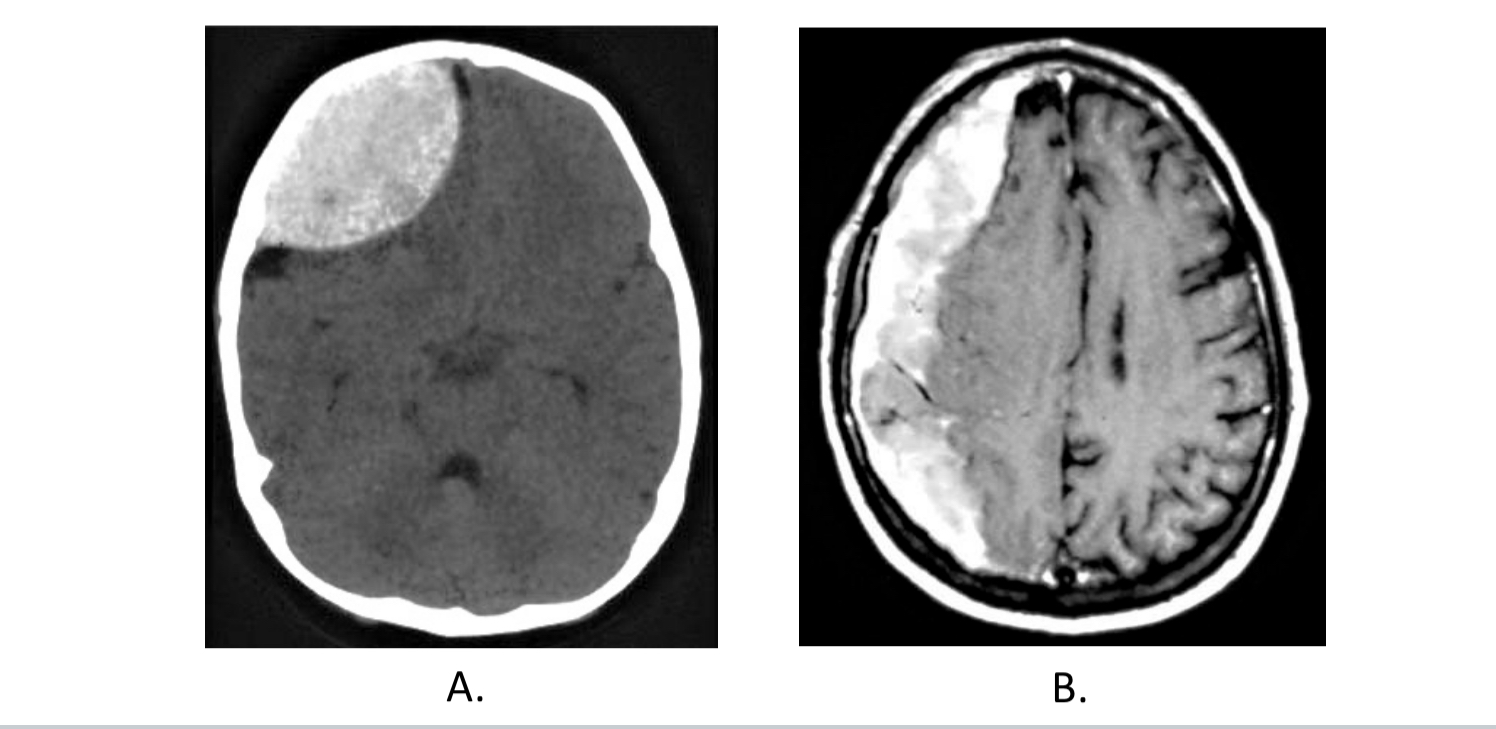

A. Epidural hematoma; B. Subdural hematoma